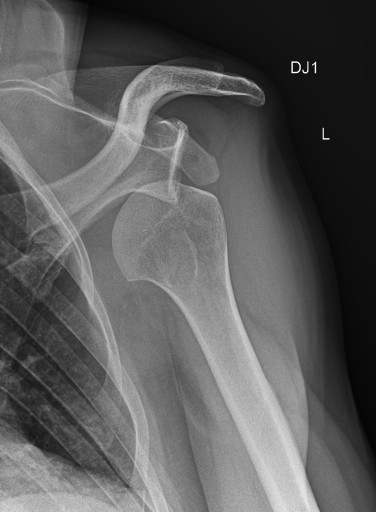

Вернувшись в аппартаменты и посмотрев на себя в зеркало я понял, что плечо само на место не встанет и вообще непонятно, что там, перелом или вывих, делать было нечего — вызвал скорую. Скорая приехала и отвезла меня в больницу в Зёльдене. Больница оказалась прямо у подъёмника, на который я так спешил. Сделали рентген — к счастью, ничего не было сломано, оказался обычный вывих, который мне сразу вправили. На всякий случай сделали ещё и МРТ, прописали обезболивающее, сказали, что купленные ски-пассы можно сдать и вернуть деньги за оставшиеся неиспользованные дни. Дали повязку на руку, которую нужно носить три недели, и отпустили домой.